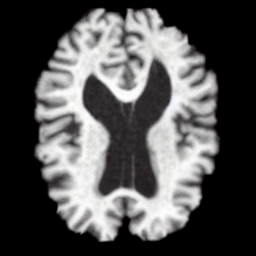

ADNI Brain MRI

ApoE Sx A B S V X

ApoE Sx Sex A Age B Brain S Slice V Ventricle X Image

What if the brain age had been different?

ADNI age traversal

5590

What if the ventricle volume had been different?

Ventricle volume traversal

01

87% FID Reduction

50% MAE Reduction

High-fidelity MRI generation with precise attribute control on age, brain volume, and ventricle volume.